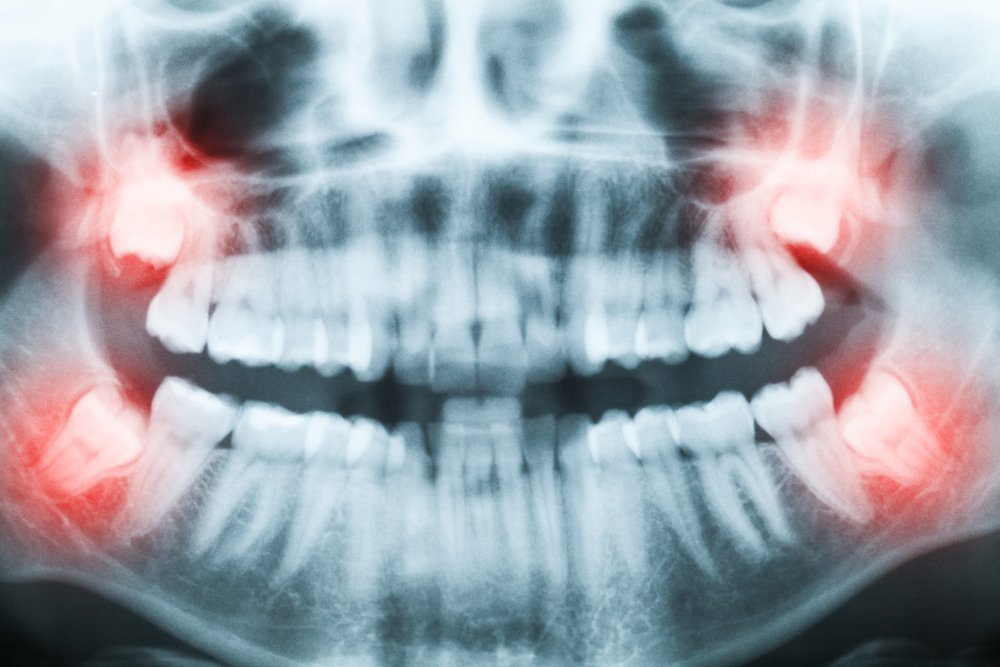

Radiografia

La un simplu control de rutină, stomatologul tău poate observa că ceva nu este în regulă, dar nu își poate da seama ce este înăuntrul gingiilor tale. Prin urmare, îți va recomanda o radiografie dentară în stabilirea unui diagnostic și, mai apoi, în pașii de urmat în timpul operației. Este posibil ca gura ta să fie prea mică pentru ca molarii de minte să se dezvolte normal sau măselele să crească în gingie într-o direcție greșită, afectând rădăcina altor dinți sau chiar osul arcadei.

Se poate întâmpla ca decizia medicului de a face extracția să nu vină foarte repede, pentru că sunt situații în care este nevoie de monitorizarea evoluției molarilor de minte. Uneori poate dura și câteva luni. Dacă între timp începi să ai dureri, observi umflături sau simți un miros neplăcut din zona în care se află măseaua, nu ezita să-i spui stomatologului tău.